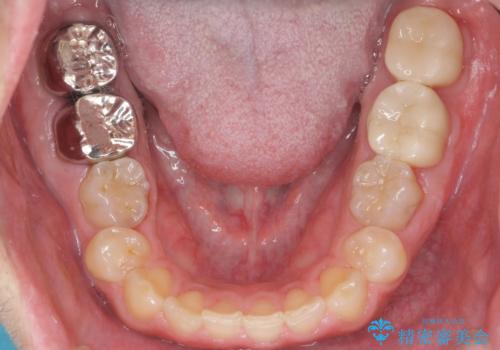

- 口の中を予算の範囲内でできるだけきれいにしたいとのことで来院された患者様です。

矯正治療と虫歯治療を組み合わせてご提案しましたが、ご予算との兼ね合いで虫歯治療のみを行うこととなりました。

奥歯は十分な歯の高さがなかったため、クラウンをかぶせる前に歯周外科治療で歯の高さを出しています。

歯科に通うようになってから磨き残しの状態も改善されていきました。